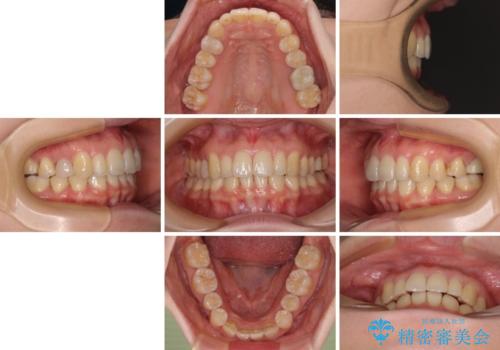

歯列のバランスが悪く、インビザライン矯正特有の奥歯の噛みにくさがなかなか改善されず、治療期間が長期化してしまいました。